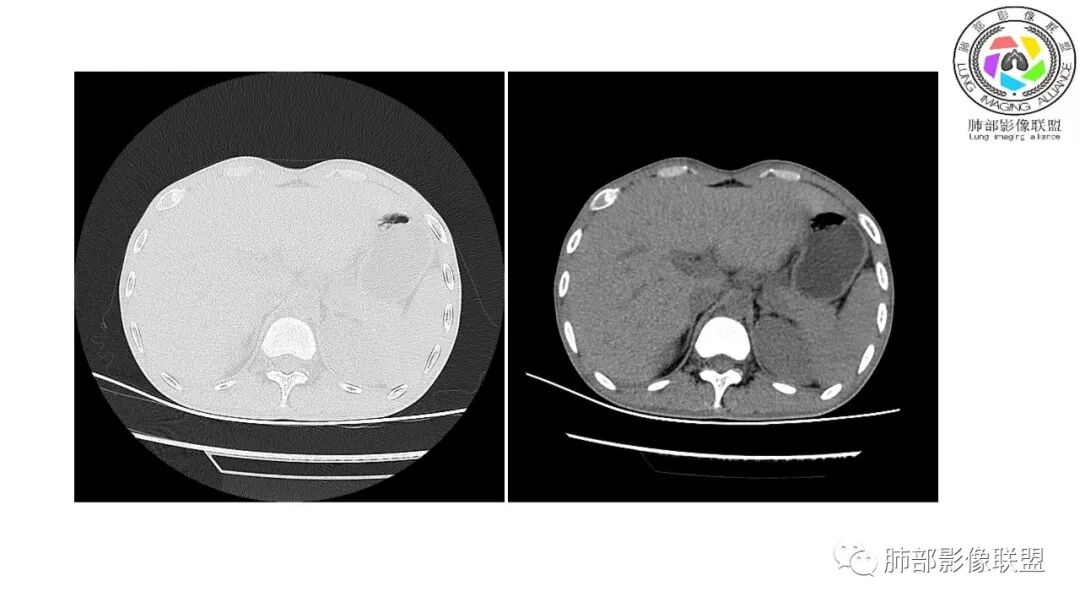

影像与临床:1.青年男性,HlV阳性,颜面部皮疹(未提供皮疹图像)、发热(高热),实验室CRP、PCT高,T-Spot阴性。2.右肺下叶空洞结节,壁厚不均,边界清楚,其内线状影,未见液平及钙化,未见卫星灶,纵隔淋巴结增大,双侧腋窝见增大淋巴结。心腔内低密度提示贫血可能。肝脾影增大,未见结节影及块影。腹膜后见多发增大淋巴结。

综合分析:本例肺部影像学改变并不具有特征性,空洞性病灶须与多种疾病鉴别,但年轻HIV阳性患者,高热,皮疹,肝脾增大,纵隔、腋窝、腹膜后见多发增大淋巴结等都强烈提示马尔尼菲篮状菌感染的可能性。